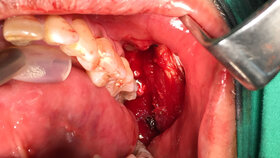

Wenn ein Mundhöhlenkrebs oder entsprechende Vorstadien entdeckt werden, sollten die betroffenen Stellen möglichst chirurgisch entfernt werden, um die Entwicklung zu einem etablierten Mundhöhlenkrebs zu verhindern, heißt es weiter. „Wenn die Geschwüre in Frühstadien komplett chirurgisch entfernt werden, liegt die Krebsüberlebensrate bei annähernd 100 Prozent“, erklärt DGMKG-Sprecher Prof. Dr. Dr. Hendrik Terheyden der Patientenschaft.

„Es bedarf großer Erfahrung, um gutartige Mundschleimhautveränderungen von den potenziell bösartigen Veränderungen per Blickdiagnose abzugrenzen“, betont Wiltfang. „Deshalb sollte eine chirurgische Exzision der kompletten Veränderung als Gewebeprobe mit anschließender mikroskopischer Untersuchung erfolgen.“ Etablierter Mundkrebs gehört zu den sehr malignen Krebsarten des menschlichen Körpers, bei dem die 5-Jahres-Überlebensrate bei Männern lediglich bei 52 Prozent und bei Frauen bei 62 Prozent liegt.